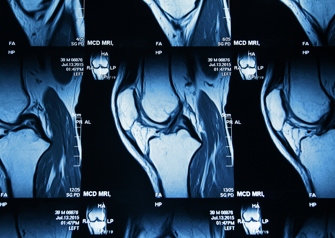

Dr. Adam Yanke, a sports medicine orthopedic surgeon at Midwest Orthopaedics at Rush, recently published new research centered around clinical outcomes following microfracture surgery of the knee. Microfracture surgery is an arthroscopic procedure used to treat small- and medium-sized cartilage defects, the clinical results of which have been mixed to date. The purpose of the studies was to evaluate patient-reported outcomes (PROs) after microfracture surgery. The articles were published in Orthopaedic Journal of Sports Medicine and The Journal of Knee Surgery.